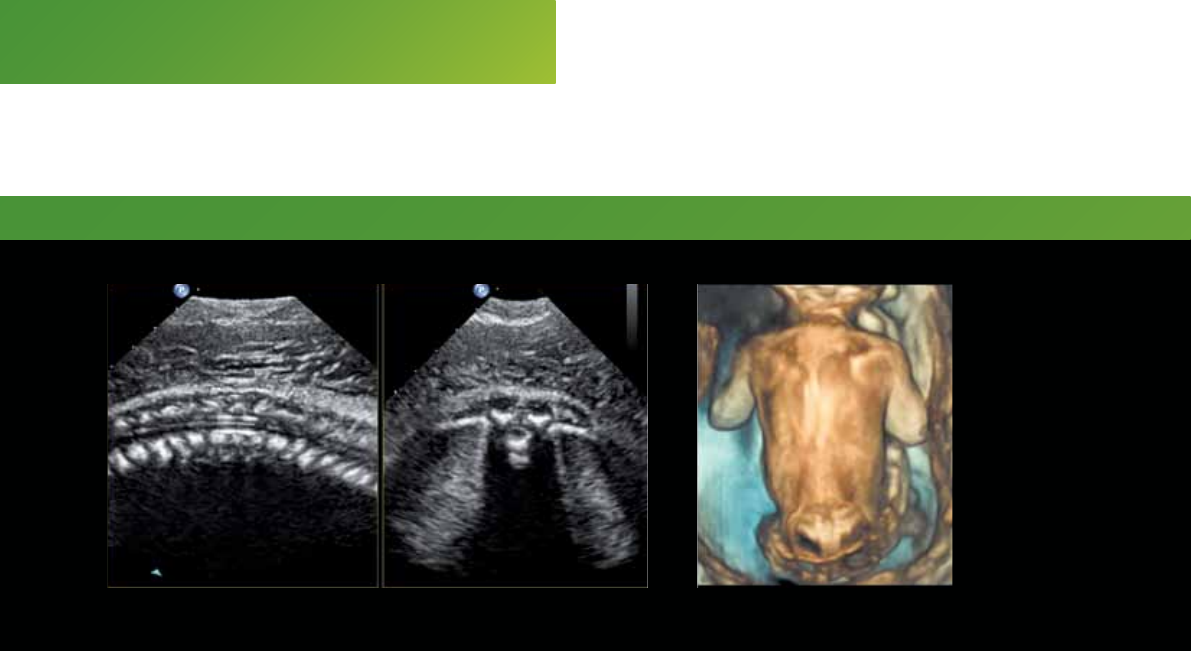

Fetal spine – Live xPlane Spina bifida

26-week gestation 24-week gestation

Bring your most challenging

cases to EPIQ 7 with our

PureWave solutions from

gynecological surveys to the

rst trimester through third

trimester exam.